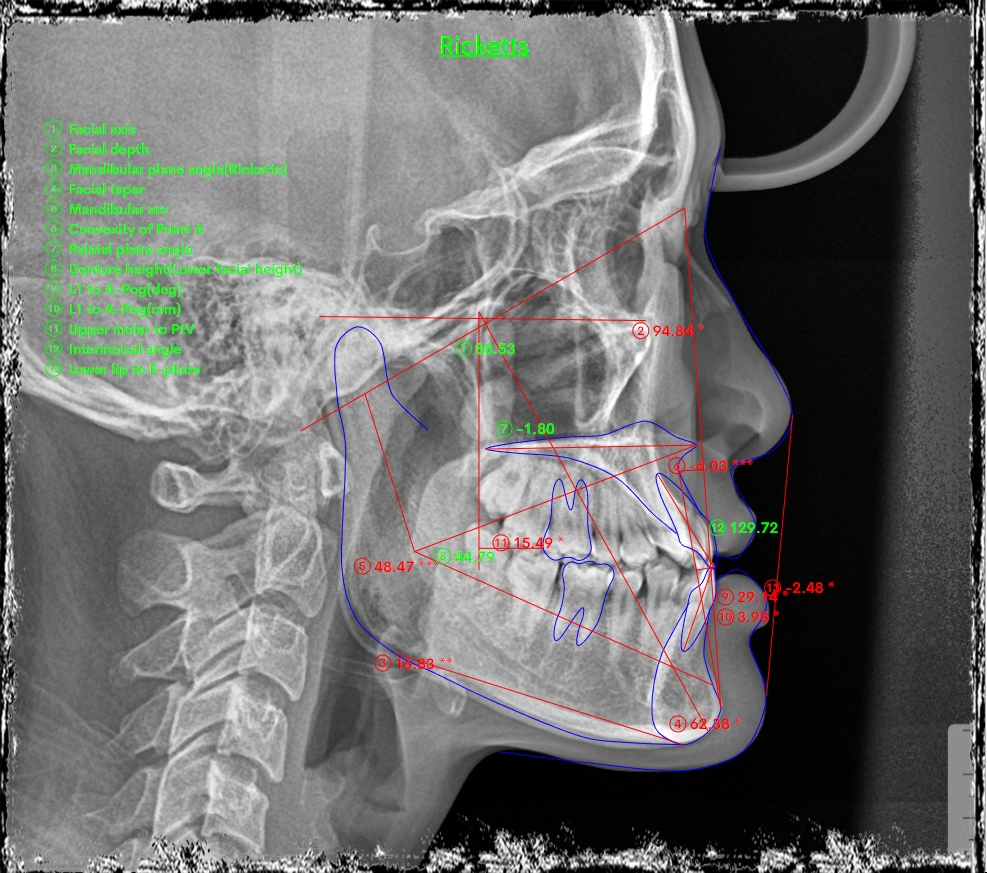

Trên kết quả chụp phim xquang mặt nghiêng cephalometric chuẩn hóa, cho kết quả sai hình xương hạng III (mặt lưỡi cày), trục răng cửa trên và cửa dưới đã bù trừ nhiều.